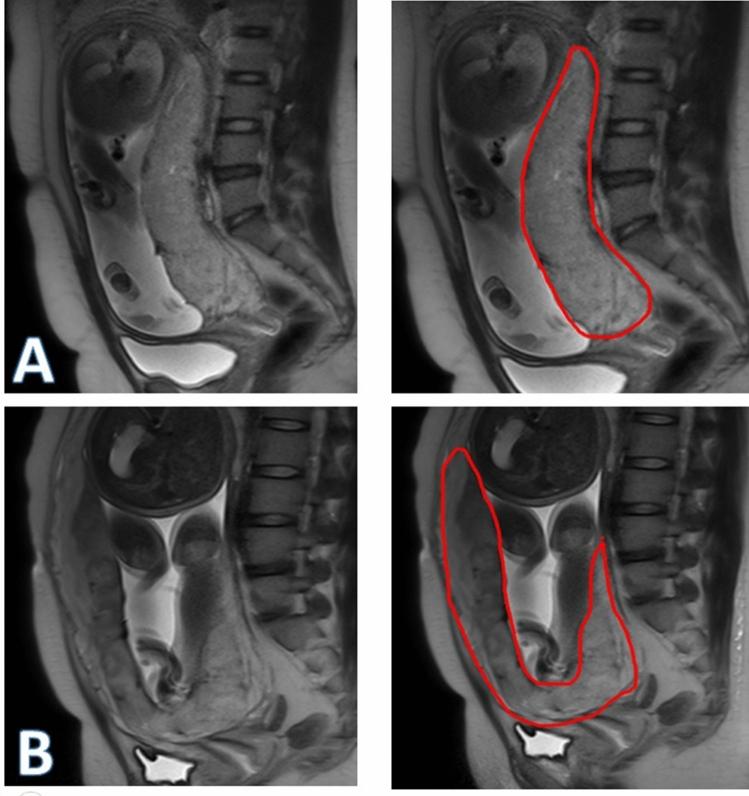

We aimed to establish a computerized diagnostic model to predict placenta accrete spectrum (PAS) disorders based on T2-weighted MR imaging. We recruited pregnant women with clinically suspected PAS disorders between January 2015 and December 2018 in our institution. All preoperative T2-weighted imaging (T2WI) MR images were manually outlined on the picture archive communication system terminal server. A nnU-Net network for automatic segmentation and the corresponding radiomics features extracted from the segmented region were applied to build a radiomics-clinical model for PAS disorders identification. Taking the surgical or pathological findings as the reference standard, we compared this computerized model's diagnostic performance in detecting PAS disorders. In the training cohort, our model combining both radiomics and clinical characteristics yielded an accuracy of 0.771, a sensitivity of 0.854, and a specificity of 0.750 in identifying PAS disorders. In the testing cohort, this model achieved a segmentation mean Dice coefficient of 0.890 and yielded an accuracy of 0.825, a sensitivity of 0.830 and a specificity of 0.822. In the external validation cohort, this computer-aided diagnostic model yielded an accuracy of 0.690, a sensitivity of 0.929 and a specificity of 0.467 in identifying placenta increta. In the present study, a machine learning model based on preoperative T2WI-based imaging had high accuracy in identifying PAS disorders in respect of surgical and histological findings.

我们旨在建立一个基于 T2 加权磁共振成像(T2WI)的计算机诊断模型,以预测胎盘植入谱(PAS)疾病。我们在机构中招募了 2015 年 1 月至 2018 年 12 月期间临床怀疑患有 PAS 疾病的孕妇。所有术前 T2WI 磁共振成像(T2WI)图像均在图像存档通信系统终端服务器上手动勾画。应用 nnU-Net 网络进行自动分割,并从分割区域提取相应的放射组学特征,以建立用于 PAS 疾病识别的放射组学-临床模型。以手术或病理结果为参考标准,我们比较了计算机模型在检测 PAS 疾病方面的诊断性能。在训练队列中,我们的模型结合了放射组学和临床特征,在识别 PAS 疾病方面的准确率为 0.771,敏感度为 0.854,特异度为 0.750。在测试队列中,该模型的分割平均 Dice 系数为 0.890,准确率为 0.825,敏感度为 0.830,特异度为 0.822。在外部验证队列中,该计算机辅助诊断模型在识别胎盘植入方面的准确率为 0.690,敏感度为 0.929,特异度为 0.467。在本研究中,基于术前 T2WI 成像的机器学习模型在手术和组织学发现方面具有很高的识别 PAS 疾病的准确性。